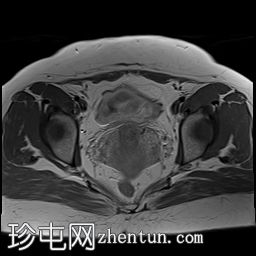

冠状位

T1加权像

可见子宫外腹腔内妊娠囊,内含胎儿组织。

该妊娠囊向后推移子宫,并与剖宫产瘢痕凹陷处紧密相连。

该妊娠囊与相关肠袢无法分离。可见其与性腺血管密不可分,且性腺血管明显突出。

胎盘位于妊娠囊后方,紧贴子宫前壁。

沿妊娠囊下缘可见一处异质性局灶性积液,最大轴向尺寸约为 8.4 × 5.5 cm,T1 加权像呈异质性高信号,T2 加权像呈异质性中等信号,T1 脂肪抑制序列未见信号下降,提示为血液成分。该积液压迫膀胱。

子宫体积增大,后倾,子宫内膜厚度约 1 cm,子宫下段前壁可见局灶性变薄(既往子宫瘢痕)。子宫连接区完整,未见肌层肿块。可见子宫内膜腔边缘有血性分泌物。